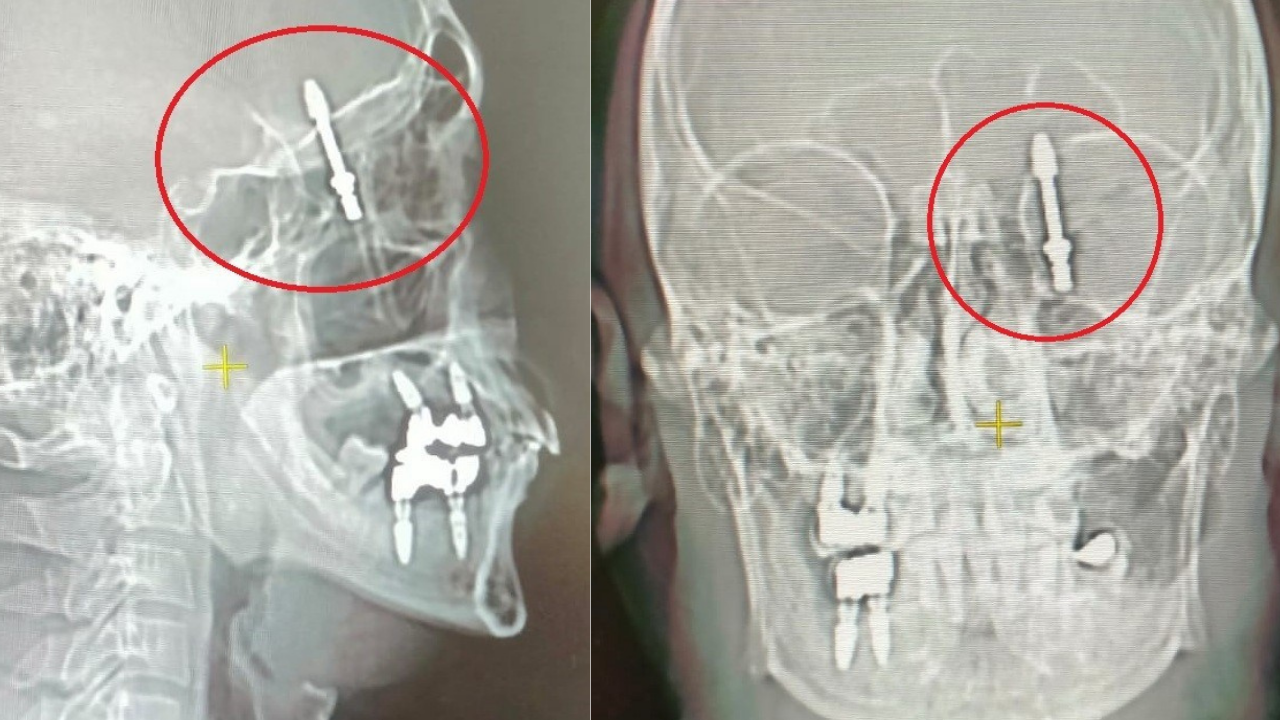

Nilüfer ilçesi. Diş tedavisi için gittiği özel klinikte yaptırdığı implant işlemi sonrası hayatı altüst olan Ramazan Yılmaz (40), iki yıldır adaletin yerini bulmasını bekliyor. İddiaya göre, diş hekimi A.D., tedavi sırasında yaptığı hatalı müdahaleyle implant vidasını çene kemiğini delip kafatasına kadar ilerletti.

Baygınlık geçiren Yılmaz, kliniğin kendi aracıyla hastaneye kaldırıldı. Tomografide vidanın beynine kadar saplandığı tespit edildi. Acil olarak ameliyata alınan Yılmaz, saatler süren operasyonla ölümden döndü.